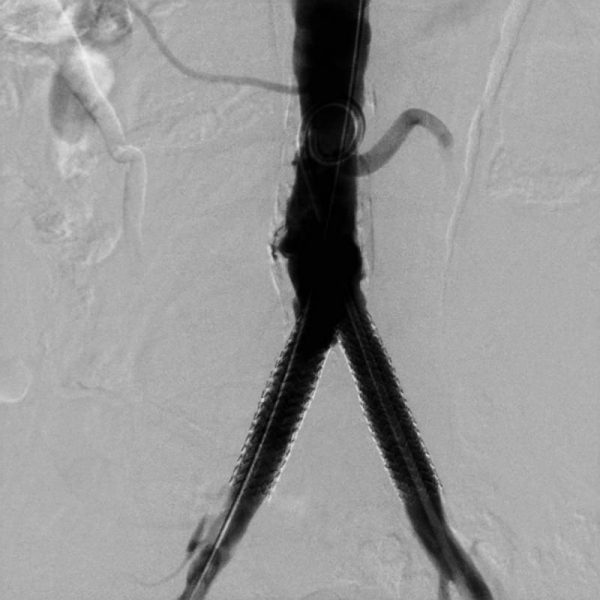

После успешной одновременной имплантации стентов сужения были полностью устранены, кровоснабжение нижних конечностей восстановлено (финальный результат представлен на заключительном фото).

Это направление высокотехнологичной медицинской помощи является весьма перспективным. Оно нацелено на достижение оптимального результата при одновременном снижении количества возможных осложнений по сравнению с открытой масштабной реконструктивной сосудистой операцией, которая была бы показана таким пациентам при отсутствии возможности эндоваскулярной коррекции.